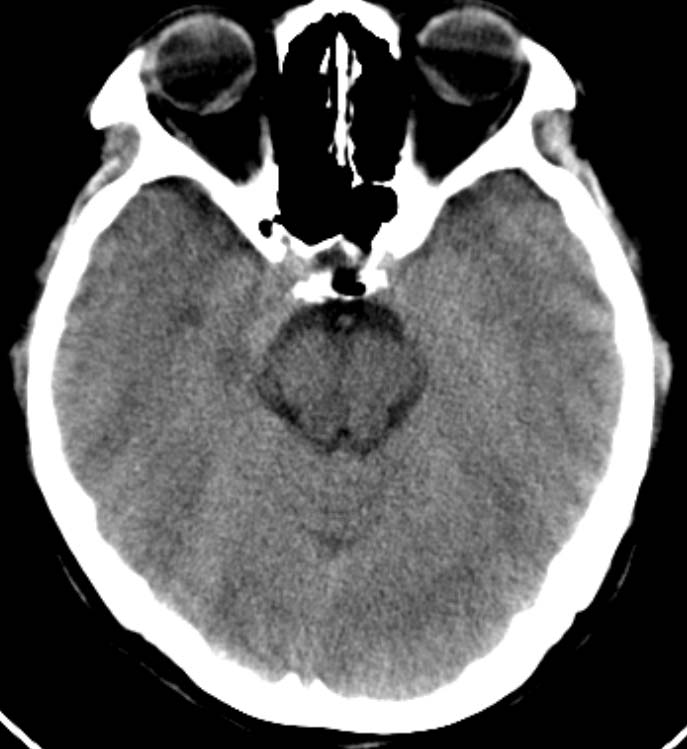

标题: CT16631:女,46岁,头痛数月。 [打印本页]

标题: CT16631:女,46岁,头痛数月。

女,46岁,头痛数月。求助战友。。。。。。。。。。。。

其余颅脑层面未见异常。

考虑脉络裂囊肿或蛛网膜囊肿可能,建议加薄扫

支持 右侧脉络膜裂囊肿。

右侧脉络膜囊肿可能性大

mri结果为考虑:蛛网膜囊肿